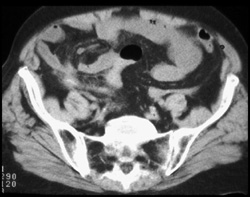

Appendiceal Abscess